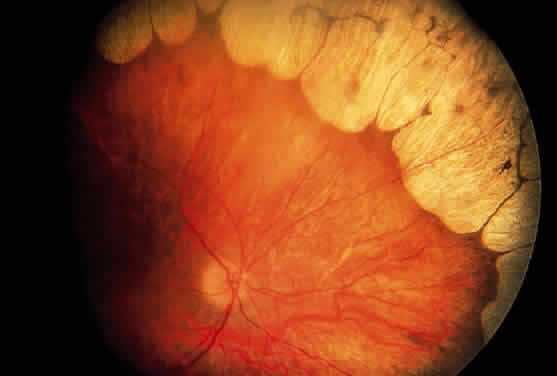

During late childhood, sharply demarcated, circular areas of chorioretinal degeneration in the midperiphery can be detected. There may be increased pigmentation around the margins of these lesions. During the second decade, the lesions enlarge, coalesce, and extend toward the posterior pole of the retina (Fig. 8). By the third decade, much of the retina is involved, although foveal lesions are rarely present until very late in the course of the disease. Histologic examination of an affected retina has shown focal areas of photoreceptor atrophy with adjacent retinal pigment epithelial hyperplasia. Electron microscopy has revealed mitochondrial abnormalities of the photoreceptors.114